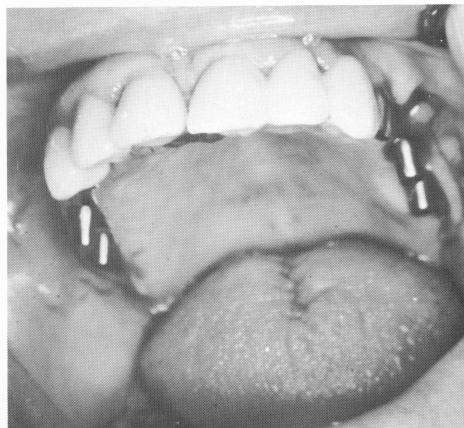

Fig. 15-101. Blade implants were set into the two posterior edentulous areas.